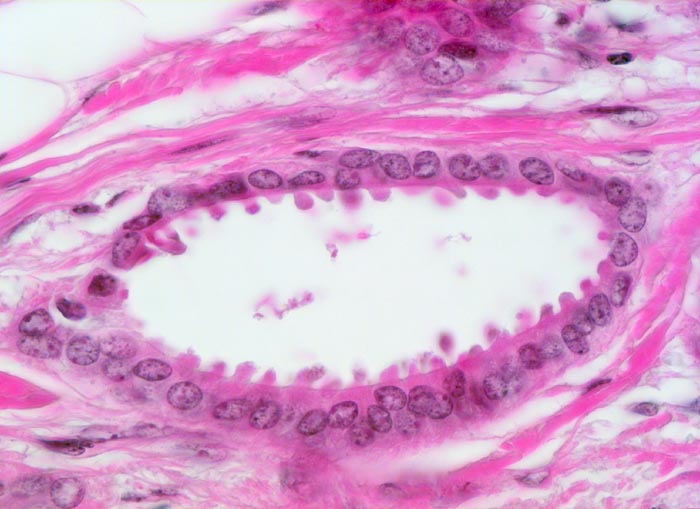

PathoPic – image database / PathoPic ID 3638 - tubuläres Karzinom

tubuläres Karzinom

maligner Tumor

Mamma

Tubuläre einreihige Karzinomdrüse ohne Basalmembran. Die Tumorzellen zeigen auffallende apikale Ausziehungen des Zytoplasmas (Snouts). Die Tumorzellkerne sind auffallend bland. Eine Myoepithelschicht fehlt.

Positive Familienanamnese für Mammakarzinom. Tumorverdächtiger Herd in der rechten Mamma.